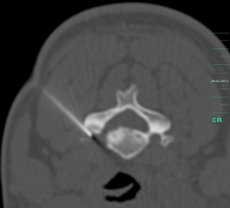

Die CT-gestützte Facettengelenkinfiltration bzw. - blockade ist ein interventionell-neuroradiologisch-schmerztherapeutisches Verfahren, um schmerzhafte, arthrotisch veränderte Facettengelenke (syn. kleine Wirbelgelenke) zu behandeln. Dabei wird das Wirbelgelenk mit einer dünnen Nadel unter CT-Kontrolle direkt punktiert und ein Lokalanästhetikum mit einem entzündungshemmenden Mittel kombiniert injiziert.